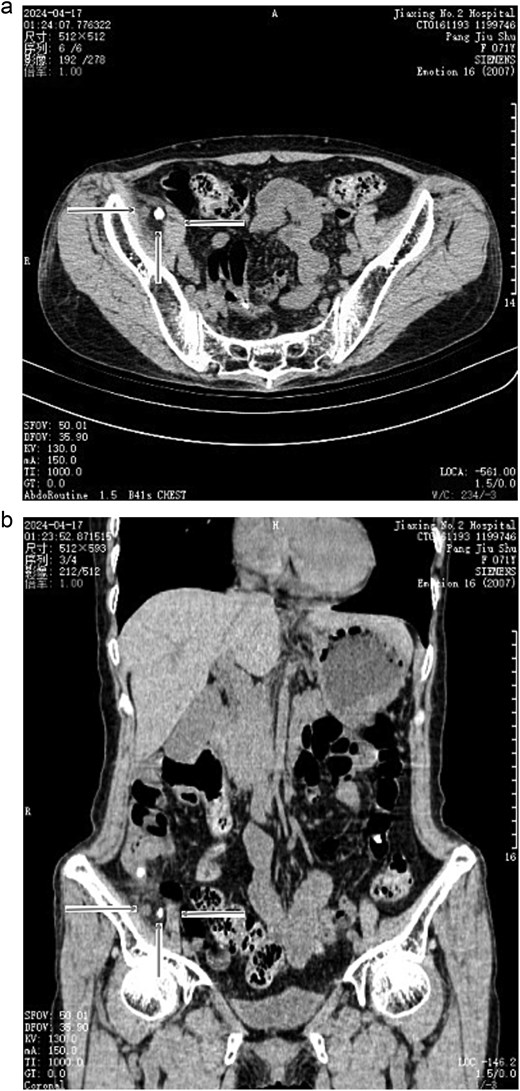

A 71-year-old female, with a body mass index (BMI) of 17.58 kg/m2, was admitted to the hospital for 2 days, due to abdominal pain. Abdominal physical assessment revealed a flat and soft abdomen, weak abdominal muscles, tender right lower quadrant, and local muscle guarding with mild rebound tenderness. Blood tests revealed white blood cells of 7.3 × 109/L, with neutrophil 85.5%, and abdominal computed tomography (CT) indicated acute appendicitis and calcification beside the appendix (Fig. 1). A laparoscopy examination was conducted under general anesthesia. Intraoperatively, a hernia on the lateral side of the right psoas muscle was observed, with the appendix herniating into the hernial sac. A small amount of pus was observed in the right iliac fossa. Post-appendectomy, adhesion between the appendix and hernial sac was separated, and the appendix was then removed. The hernial sac was exposed with a 3 cm depth and a 2 × 1.5 cm neck. The hernial sac was closed with interrupted sutures (Fig. 2). Specimen anatomy revealed fecal stones in the appendix and calcification in the mesoappendix. The pathology indicated acute suppurative appendicitis with appendicular peritonitis.

(a) Preoperative CT scan indicated acute appendicitis and calcification beside the appendix (transverse section). →: Appendix; ↑: Calcification; ←: Psoas muscle. (b) Preoperative CT scan indicated acute appendicitis and calcification beside the appendix (coronal section). →: Appendix; ↑: Calcification; ←: Psoas muscle.